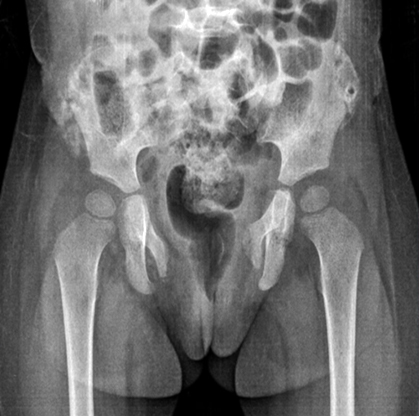

Al ingreso la paciente se encontraba hemodinámicamente inestable, hipotensa, con taquicárdica, y demás signos vitales normales. Al examen físico se observaron marcas de una llanta sobre cresta ilíaca derecha, laceraciones y distensión abdominal. Se tomaron gases arteriales y se constató hiperlactatemia leve, base exceso en -10, y hemoglobina en 6,7. Se realizaron maniobras de reanimación y se trasladó a la sala de cirugía para colocarle un tutor externo en pelvis. Se precisó ingreso en unidad de cuidados intensivos. Se evidenció fractura pélvica inestable Torode y Zeig IV, de libro abierto con fractura asociada a alerón ilíaco (fig. 1).

Fig. 1 Fractura pélvica inestable Torode y Zeig IV, libro abierto con fractura asociada a alerón ilíaco.